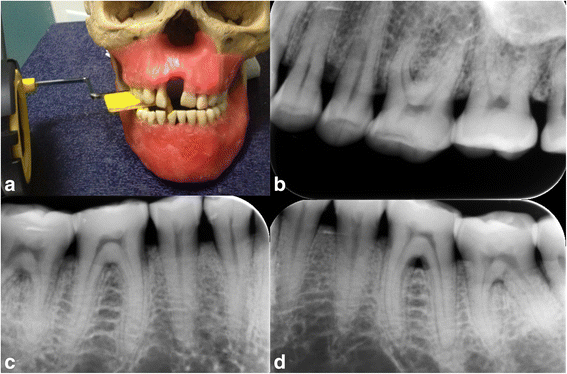

Methods: The study material comprised 12 dry skulls with maxilla and mandible. Artificial defects (dehiscence, tunnel, and fenestration) were created on anterior, premolar and molar teeth separately using burs. In total 14 dehiscences, 13 fenestrations, eight tunnel and 16 without periodontal defect were used in the study. These were randomly created on dry skulls. Each teeth with and without defects were images at various vertical angles using each of the following modalities: a Planmeca Promax Cone Beam CT and a Digora photostimulable phosphor plates. Specificity and sensitivity for assessing periodontal defects by each radiographic technique were calculated. Chi-square statistics were used to evaluate differences between modalities. Kappa statistics assessed the agreement between observers. Results were considered significant at P < 0.05.